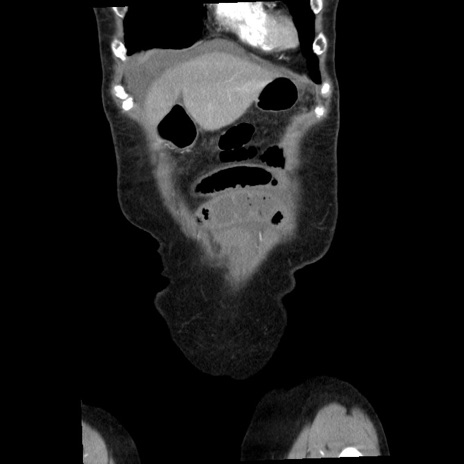

横断像

【症例】80歳代女性

【主訴】腹痛

【現病歴】8時間前から腹痛あり来院。

【既往歴】糖尿病、脂質異常症、子宮体癌にて子宮全摘術

【身体所見】意識清明・会話良好だが腹痛で苦悶様、全腹部にわたって反跳痛と圧痛あり

【データ】WBC 13600、CRP 0.14、LDH 224、CK 90